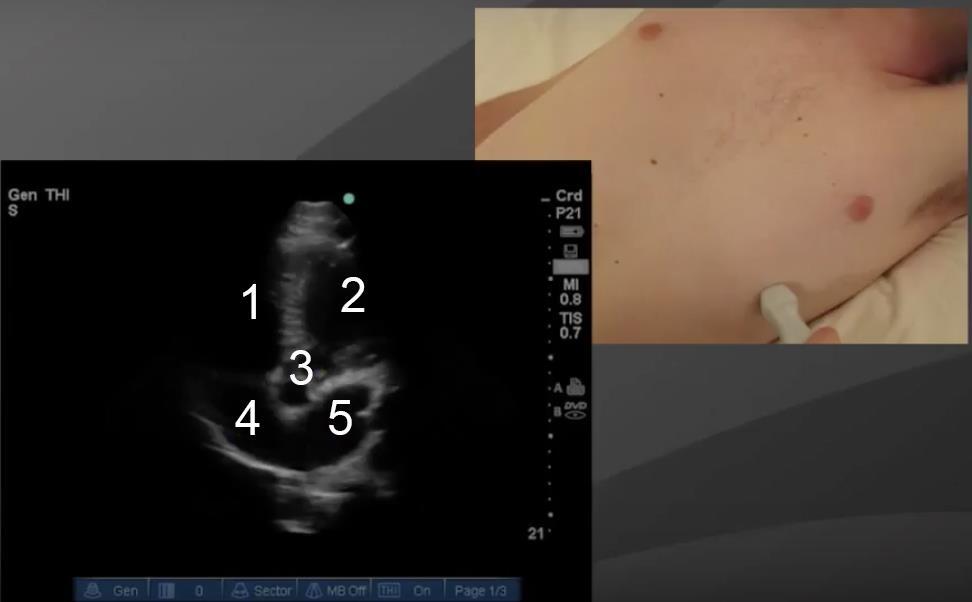

Image : Cœur, coupe apicale 5 cavités

1. Ventricule droit (VD)

2. Ventricule gauche (VG)

3. Aorte

4. Atrium droit (AD)

5. Oreillette gauche (OG)